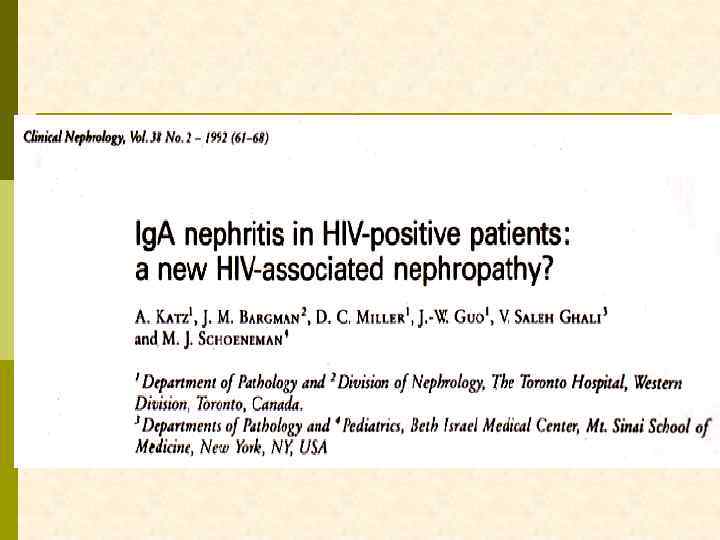

Спектр нефропатий у ВИЧ-инфицированных больных • ВИЧ-ассоциированная нефропатия (коллаптоидный вариант ФСГС) • Мезангиальный гломерулонефрит с ИК-депозитами, включая Ig. A- и нефропатию при геморрагическом васкулите • Lupus-подобный гломерулонефрит • Болезнь минимальных изменений • Мембранозная нефропатия • Мембрано-пролиферативный гломерулонефрит I типа • Парапротеиновые нефропатии: λ- или κ-/амилоид/фибриллы • Нефропатия при ТТП и ГУС • Нефропатии, ассоциированные с сочетанными инфекциями (гепатит В и С) • Острый канальцевый некроз • Аллергический интерстициальный нефрит • Кристаллонефропатии: (некоторые ингибиторы протеазы) • Почечная недостаточность и синдром Фанкони (некоторые reverse ингибиторы транскриптазы) • Саркома Капоши, инфильтративная James E. Balow, 2005 • Лимфома, инфильтративная